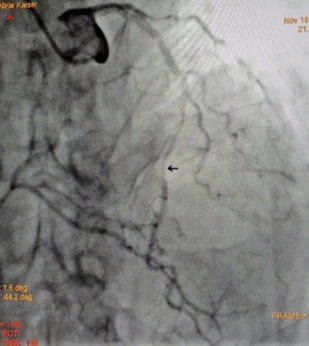

Coronary angiography showed single vessel coronary artery disease with long segment myocardial bridge in mid LAD, RCA-Totally occluded from its ostial part with retrograde filling by left system.

Figure 4: RCA-Totally occluded from its ostial part.

Figure 5: Failed PCI to RCA.

Figure 6: Long segment myocardial bridge in mid LAD (Milking Effect), during systole.

Figure 7: Long segment myocardial bridge in mid LAD during diastole.